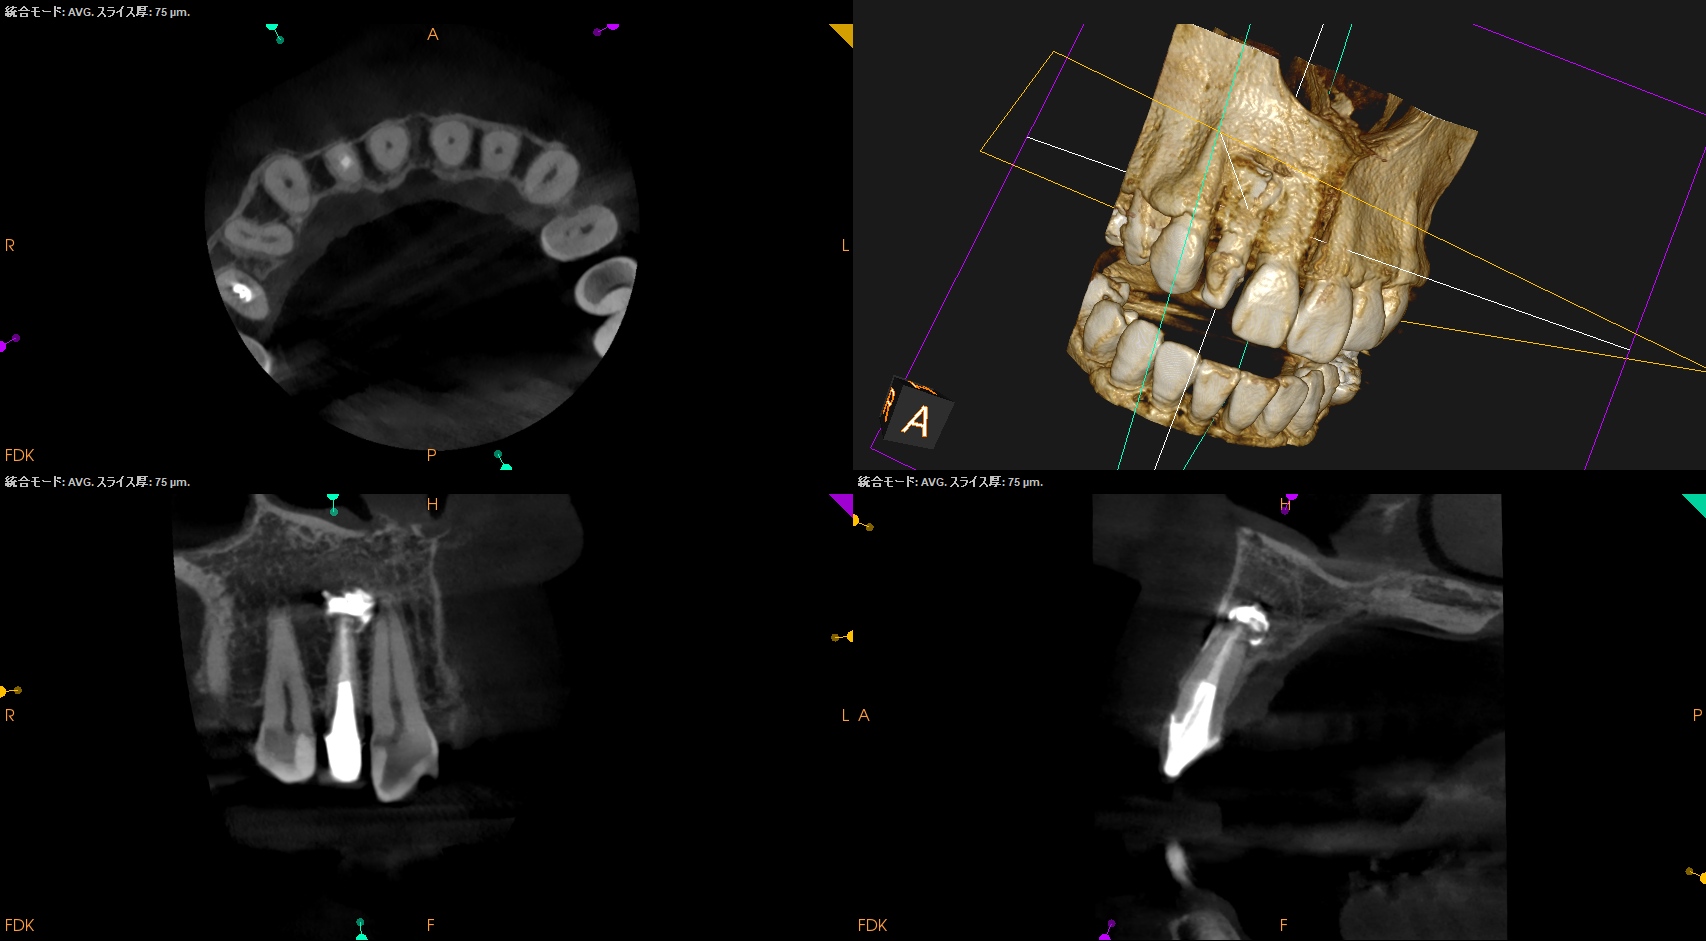

CBCT(2025.10.21)

外科は以下のように行うだろう。

Apexよりも12.5mm下方に#7のApexがあり、そこを3mm切断しようとすれば頬舌的に3.9mの切断が必要だ。

全く難しくはないだろう。